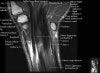

- Sagittal section

Sagittal T1 evaluates the tendons, bone marrow and relationships between the osseous structures.